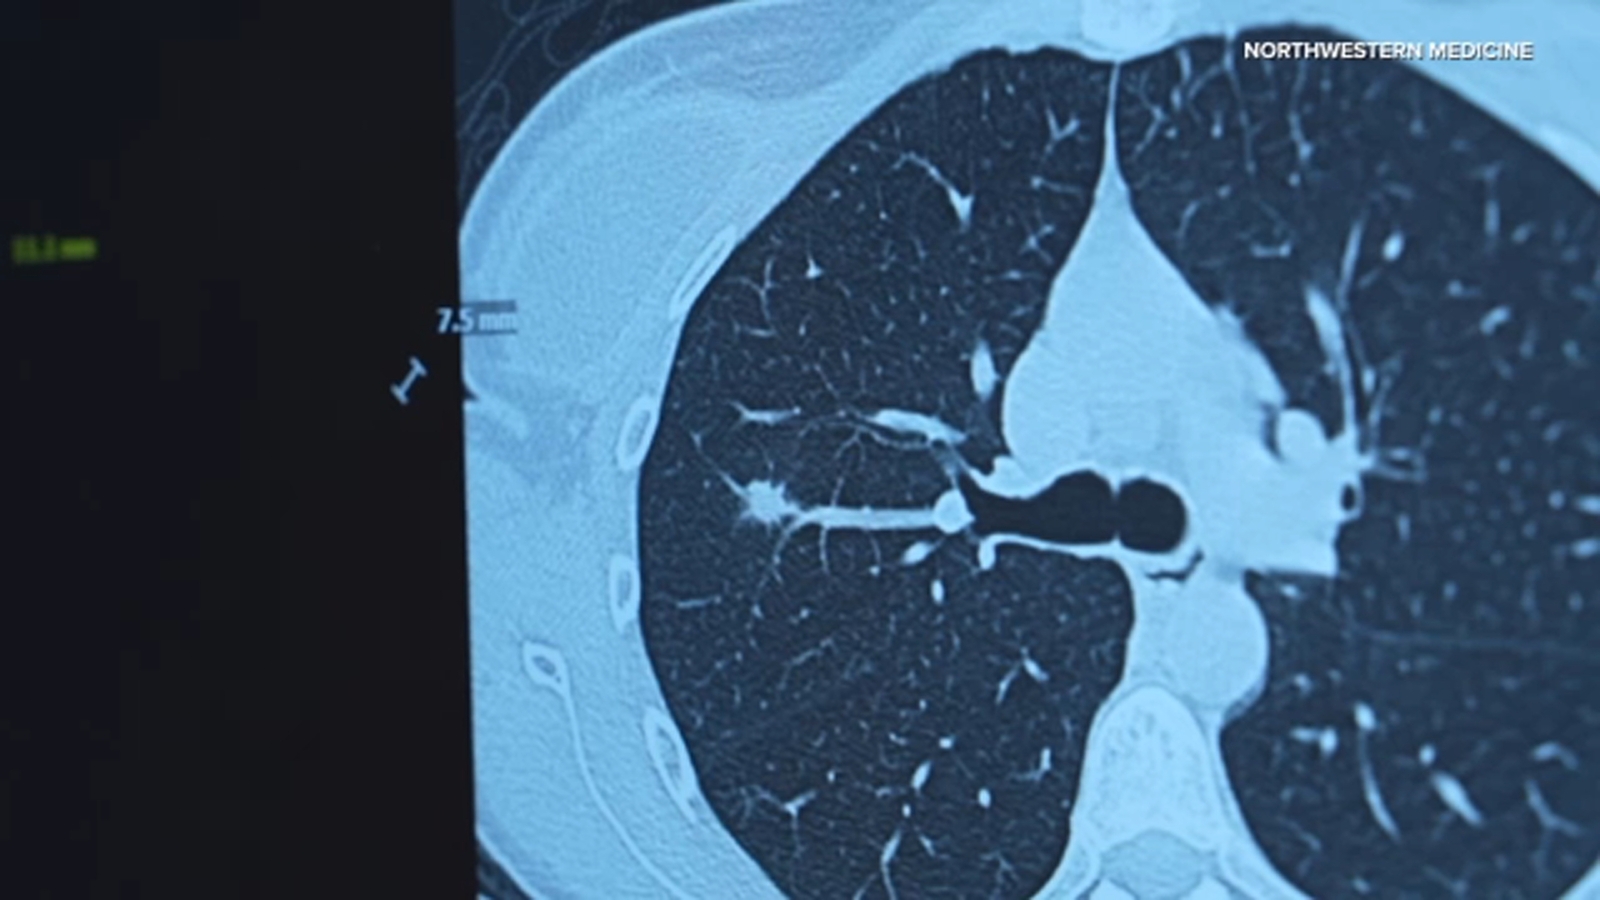

It’s why Northwestern Medicine is helping to expand low dose CT screening by launching a comprehensive lung health center to detect lung, heart and bone conditions earlier.

Northwestern Medicine said their early lung screening scan takes less than 10 seconds and doesn’t need any dyes but does provide a complete picture of the chest cavity, creating a baseline image patients can keep for life.